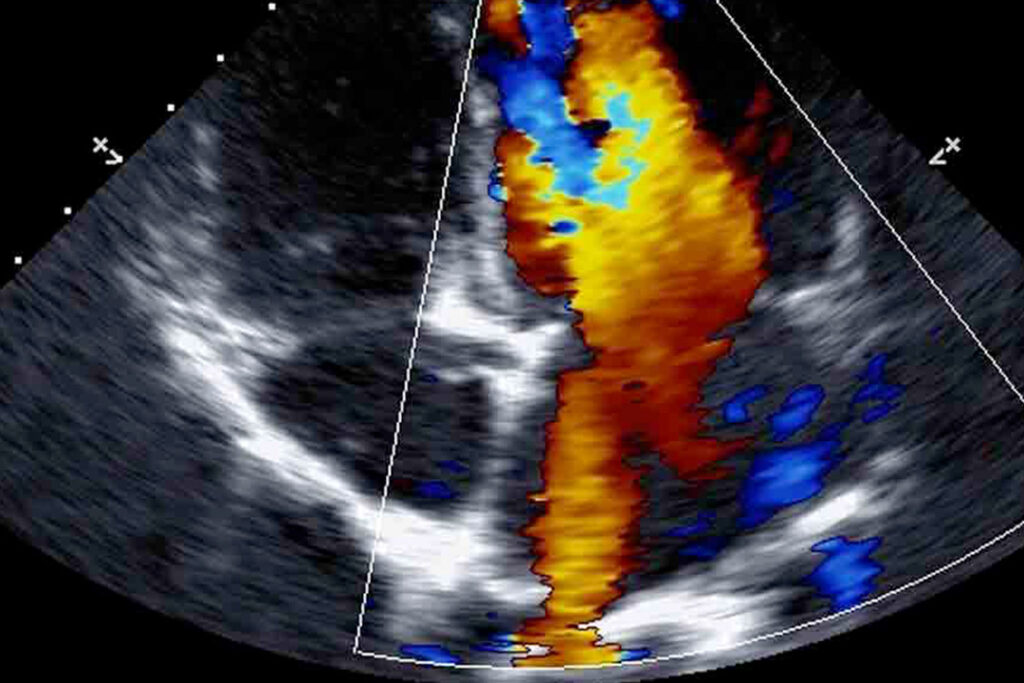

ECD venoso

- Direttore del Corso: A. Mele

- Discipline: Cardiologia, Medicina interna, Radiodiagnostica

ECD nefrologico

- Direttore del Corso: A. Zito

Discipline: Medicina d'Urgenza,

Medicina Interna,

Nefrologia, Radiodiagnostica

ECD tiroideo

- Direttore del Corso: A. Mele

- Discipline: Endocrinologia, Medicina interna, Radiodiagnostica